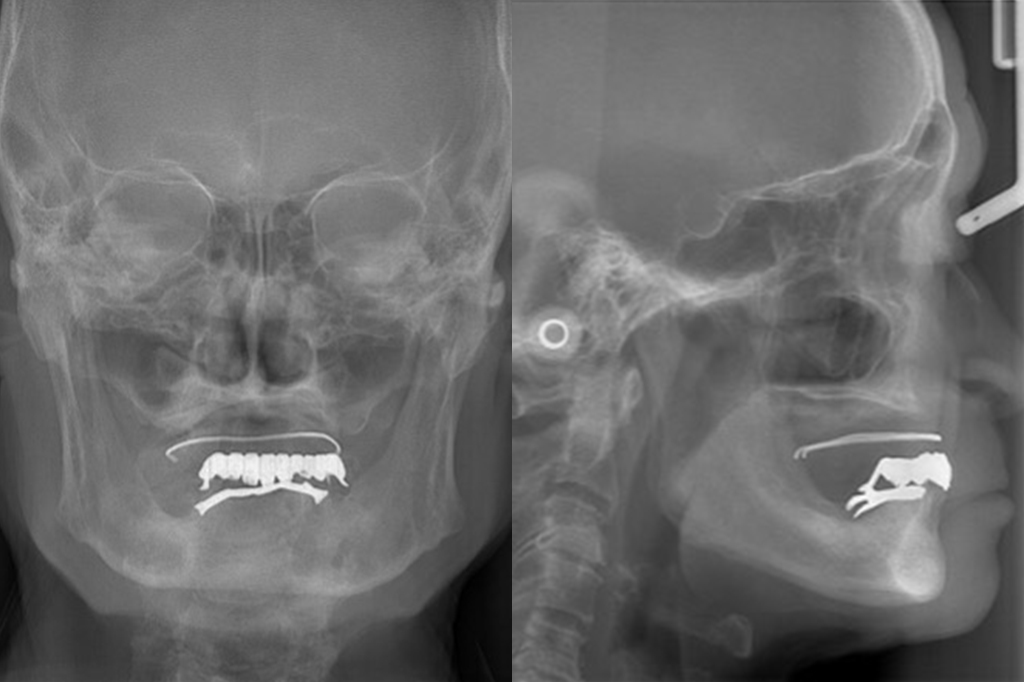

当院では義歯作製の一環として、顔貌検査、顎関節検査、顎運動検査、咀嚼機能検査等を取り入れています。

総合診断

(顔貌・CT)

- - 8,000円